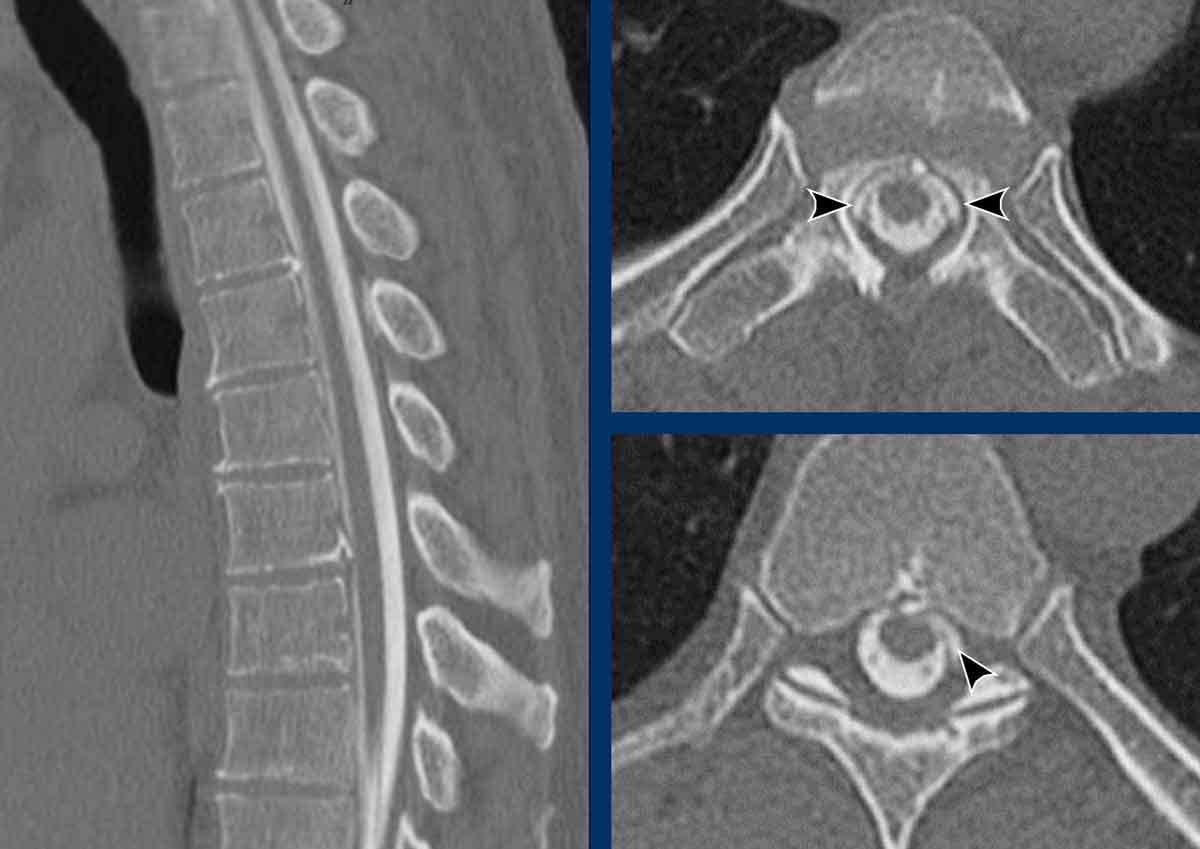

Hình ảnh

Lưu ý các tụ dịch não tủy dọc theo cột sống (đầu mũi tên).

Đây được gọi là dương tính với SLEC.

Thông thường, các chuỗi xung T1, T2 và CISS/FIESTA theo mặt phẳng đứng dọc với tái tạo mặt cắt ngang sẽ đủ để chẩn đoán SLEC.

Đôi khi, chuỗi xung STIR đứng dọc bổ sung và hình ảnh dòng chảy cine có thể mang lại lợi ích thêm.